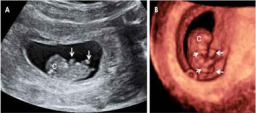

Desarrollo del feto en la semana 9